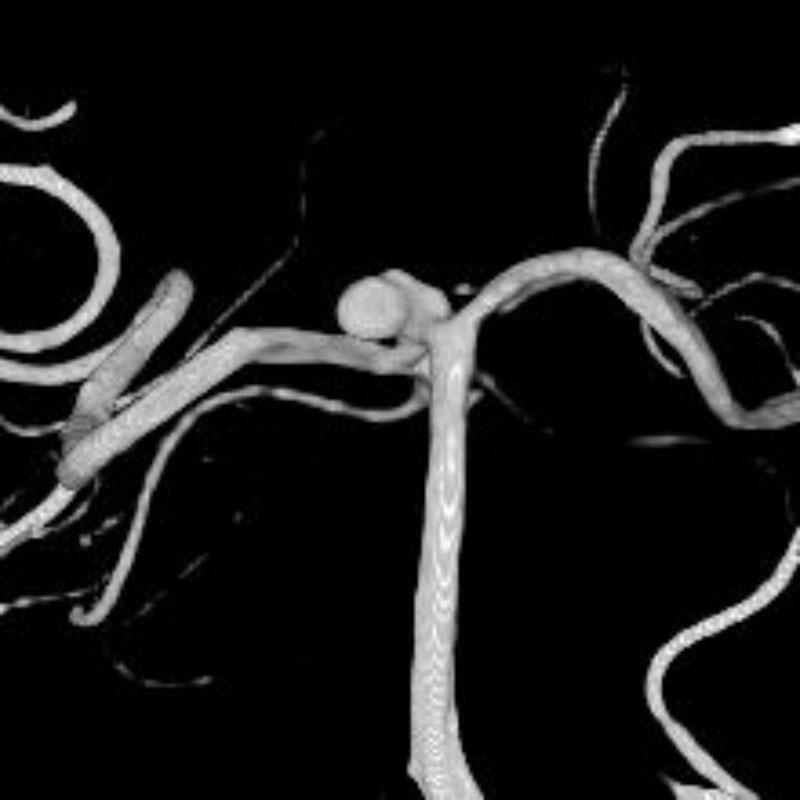

脳動脈瘤(Acom)

クリッピング術

松田/濵田/元永